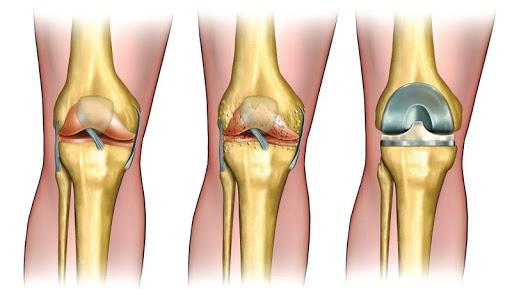

تهدف عملية استبدال مفصل الركبة الى علاج تآكل الغضروف في مفصل الركبة، الذي يحدث غالبا نتيجة لالتهاب المفاصل المزمن، على إختلاف أنواعه، خصوصا الفصال العظمي، الذي يؤدي الى تحديد قدرة المريض على تحريك مفصل الركبة، وتعتمد العملية على إستبدال المفصل المصاب بمفصل ركبة إصطناعي.

تزداد نسبة الاٍصابة بالفصال العظمي مع التقدم بالسن، حيث يحدث تضيق في الحيز المفصلي السليم، وتنكشف العظمة اٍلى تجويف المفصل، مع مرور الوقت تظهر آلام كثيرة، تصلب مفصلي وتقييدات ملحوظة في الحركة، والتي لا تتيح للرجل بأن تتحرك بشكل سليم أثناء المشي. يتم اٍجراء هذه العملية للمرضى الذين لا تتحسن حالتهم بمساعدة العلاج المحافظ (ممارسة الرياضة، المعالجة الفيزيائية أو استخدام الأدوية المضادة للاٍلتهاب)، وعندما لا يكون بوسع المريض مزاولة نشاطاته اليومية، مما يؤثر سلبا على جودة حياة المريض.

بعد إجراء تعقيم شامل لمنطقة العملية، يتم اٍحداث شق بطول 8-12 سم في الجزء الأمامي من الركبة، عند كشف الحيز في مفصل الركبة، يقوم الجراح باخراج الأنسجة الغضروفية والعظمية الزائدة، التي تؤثر سلبا على الحيز في مفصل الركبة.

يتم تعديل أسطح المفصل بحيث تستطيع احتواء المفصل الاصطناعي المركب من البلاستيك والمعدن، يتم الصاق المفصل الاصطناعي بعظمة الفخذ، الساق والرضفة، بواسطة مادة ملاطية أو مادة أخرى، تستعمل كمادة لاصقة فسيولوجية.

يتم تثبيت المفصل الاصطناعي الى عضلات الركبة والأربطة الداعمة للمفصل، من أجل الحصول على أداء حركي في المفصل بشكل مماثل للوضع الطبيعي. يتكون الجزء الملتصق بعظمة الفخذ من معدن صلب وأملس، والذي يستطيع تحمل أوزان ثقيلة. يتم تغطية المفصل بضمادة مرنة.

تختلف مفاصل الركبه الصناعيه في تصميمها و انواعها حسب احتياج المريض و حالته، الهدف عموما من مفاصل الركبه الصناعيه هو استبدال سطح الركبة المتآكل باخر صناعي، املس يمنع الالام الناتجه عن خشونه الركبه و يجعل حركه الركبه مرنة ليتمكن المريض من المشي بسهولة مرة أخرى.

ببساطه المفصل مكون جزئين مصنوعين من سبيكة معدنية تتحمل الضغوط والأحمال لمدة سنوات طويلة.

تثبت القطعتين على الأجزاء المساهمة في مفصل الركبة من أسفل عظمة الفخذ وأعلى عظمة القصبة.

تثبت بين السطحين المعدنيين قطعة مصنوعة من اللدائن البلاستيك وتسمح هذه القطعة بالحركة بنعومة ويسر.

هناك أنواع مختلفة من المفاصل منها المفاصل ذات السطح غير المتحرك وأخرى ذات سطح متحرك تسمح بحركة دوران القصبة للداخل والخارج مما يتيح حركة أكثر انسيابية ويطيل عمر القطعة البلاستيكية في المفصل، كما تختلف مدة عملية تغيير مفصل الركبة كما يوجد أنواع مفاصل للركبة ذات مفصل محوري في المنتصف يستخدم في الحالات التي تعاني من عدم ثبات واضح بسبب مشاكل بالأربطة المحيطة للركبة.

كما يوجد نوع من مفاصل الركبة يكون نصف مفصل فقط ويستخدم في حالات تآكل جهة من مفصل الركبة دون الأخرى، قد يحتاج الجراح مكونات إضافية مثل مكعبات معدنية لتعويض نقص في سطح المفصل أو كتركيب جزء إضافي لتعويض سطح عظام الصابونة الخلفي.

هناك أيضا أنواع من مفاصل الركبة الصناعية تحتاج للحفاظ علي الرباط الصليبي، أثناء الجراحة و أخرى تحتاج لاستئصاله أثناء الجراحة، يتم الكشف علي المريض وعمل إشعات خاصة لتحديد نوع المفصل المناسب لكل حالة.